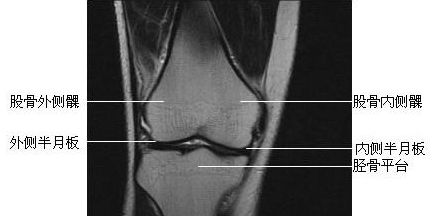

膝关节冠状面-MRI图

膝关节冠状面-MRI